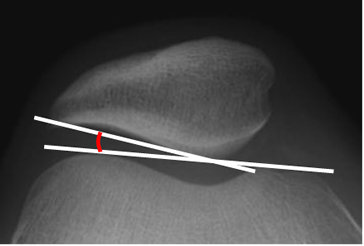

Fig 6. Angulo de congruencia.

Rx tangencial a 30º. Bisectriz del ángulo del surco (Línea blanca) y línea que une el centro del surco, con la parte inferior de la patela. (Línea roja).

Fig 7. Angulo patelofemoral.

Rx tangencial a 30º. Angulo normal, de vértice medial.